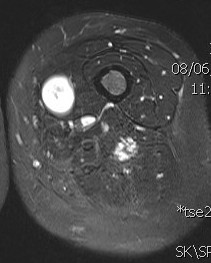

MRI

Target sign

- hypointense centrally

- hyperintense peripherally

Neurofibroma common peroneal nerve